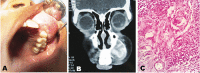

Juvenile aggressive ossifying fibroma (JAOF) is an uncommon benign lesion which is distinctly aggressive in behavior with high tendency for recurrence. It appears in early age and in 79% of patients is diagnosed before 15. It has two histological variants: psammomatoid and trabecular, with the latter being less common with a stronger tendency to recur. In this article, we present a case of trabecular JAOF, in which treatment could not be given despite the availability of all requisites for surgery and good financial status, due to parental indifference and negligence.